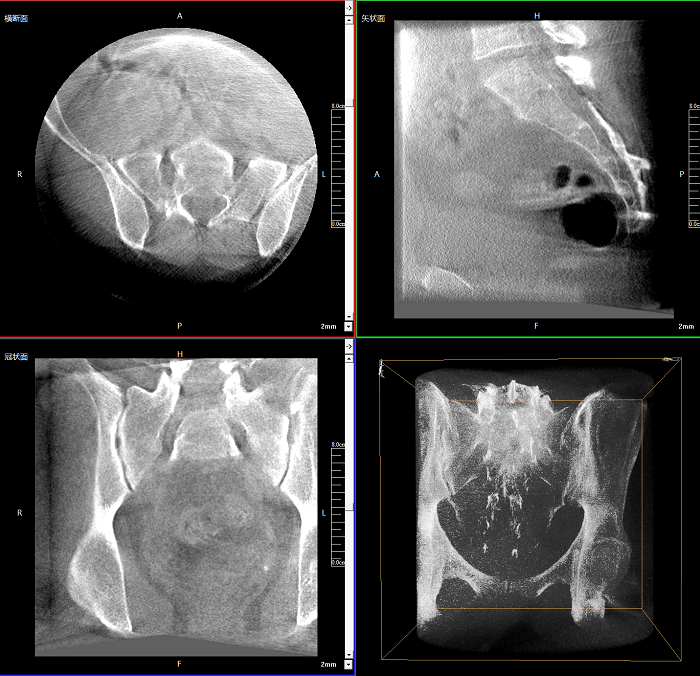

該設(shè)備可進(jìn)行快速的術(shù)中三維掃描,生成類(lèi)CT斷層圖像和立體3D圖像,保障植入物置入效果。廣泛適用于骨科、脊柱外科、矯形外科、創(chuàng)傷骨科等其他領(lǐng)域。

●極速成像僅需8秒,從數(shù)據(jù)采集結(jié)束到完成三維重建斷層影像